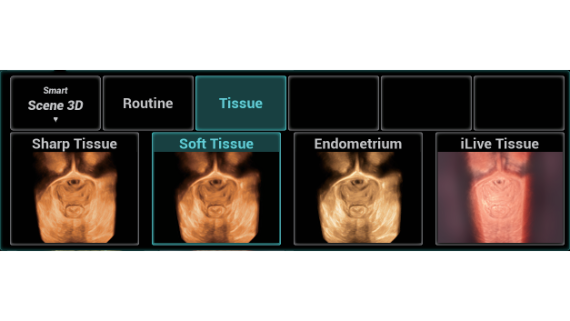

Gambar Klinis